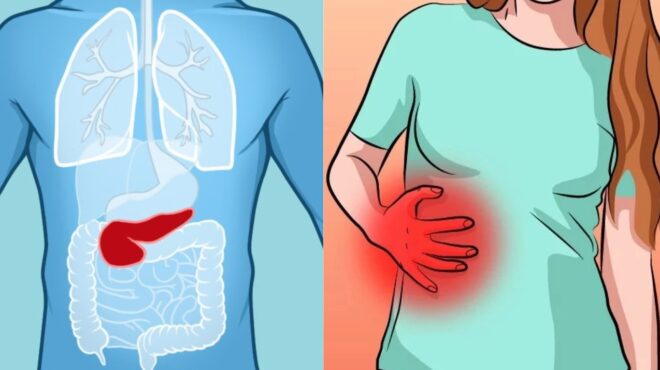

Η Παγκρεατίτιδα είναι οξεία ή χρόνια φλεγμονή του παγκρέατος. Τα οξέα επεισόδια τις περισσότερες φορές χαρακτηρίζονται από ισχυρό κοιλιακό άλγος, που ακτινοβολεί από το πάνω μέρος της κοιλίας ως την πλάτη και μπορεί να προκαλέσουν από μετρίου βαθμού διόγκωση του παγκρέατος ως δυνητικά θανατηφόρα παγκρεατική ανεπάρκεια.

Η χρόνια παγκρεατίτιδα είναι μία προοδευτική κατάσταση, που περιλαμβάνει μία σειρά οξέων επεισοδίων. Αυτά τα επεισόδια μπορεί να προκαλέσουν διακοπτόμενο ή διαρκή πόνο και μπορεί να προκαλέσουν μόνιμη βλάβη των ιστών του παγκρέατος.

Η οξεία παγκρεατίτιδα είναι μια κατάσταση αυτοπεψίας του αδένα και ενδεχομένως, των παρακείμενων οργάνων. Μπορεί να περιπλέκεται με νέκρωση, μόλυνση και ανεπάρκεια άλλων οργάνων. Το ποσοστό θνησιμότητας είναι 5 έως 10%.

Σε φυσιολογικές συνθήκες τα πεπτικά ένζυμα είναι αδρανή και ενεργοποιούνται μόνο για την πέψη των τροφών όταν φθάσουν στο λεπτό έντερο. Σε περίπτωση όμως που το πάγκρεας φλεγμαίνει, ενεργοποιούνται ενώ βρίσκονται ακόμη μέσα σε αυτό και του «επιτίθενται», καταστρέφοντας το. Η κατάσταση αυτή μπορεί να είναι οξεία ή χρόνια.

Παγκρεατίτιδα: Ποια είναι τα συμπτώματά της

Η οξεία παγκρεατίτιδα εμφανίζεται ξαφνικά με ήπιο έως έντονο πόνο στο άνω μέρος της κοιλιάς “σαν ζωνάρι” που μπορεί να αντανακλά στην πλάτη και το στήθος. Ο πόνος μπορεί να είναι σταθερός για ώρες ή και μέρες και είναι πιθανόν να χειροτερεύει με το φαγητό ή το αλκοόλ. Η κάμψη του σώματος προς τα εμπρός ή η εμβρυϊκή θέση μπορεί να παρέχει προσωρινή ανακούφιση.

Μπορεί να υπάρχει μετεωρισμένη και τυμπανισμένη κοιλιά, μια αντίσταση στην ψηλάφηση γύρω και κάτω από τον ομφαλό αλλά συχνά τα σημεία της φυσικής εξέτασης είναι ελάχιστα η και καθόλου, σε αντίθεση με τη σοβαρότητα της συνολικής εικόνας.